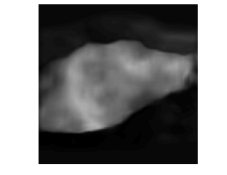

Fig. 4 shows a comparison of a representative motion field predicted by MFINc with that computed via the GS registration algorithm. We can see that the motion field produced by MFINc is smooth and has sharper motion boundaries. The reason for this might be that the used registration is more regularized due to its parametric model, where motion is defined by a grid of control points with 4x4 pixel spacing and linearly interpolated in between. This might also explain the higher error in evaluation of the flow field predicted by the network over the whole image (RefMotErrFl) than only over the liver (RefMotErrFlLiver).

a

b

c

d